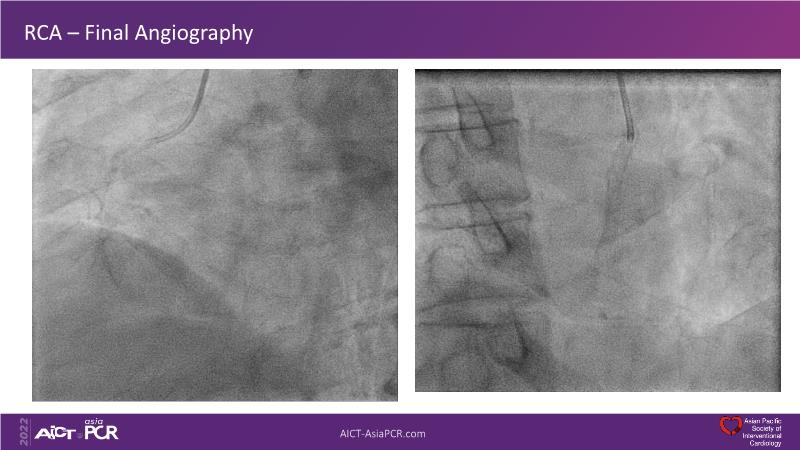

In this session, presenters describe how to use IVUS and physiology in the assessment of left anterior descending and/or left circumflex ostium in distal left main disease. Discover in the second part the general principles and clinically validated strategies for ultralow contrast coronary angiography and zero contrast percutaneous coronary intervention.

- To learn how imaging can help with strategising left main PCI, plaque preparation, device sizing and optimising results

- To learn to create contrast-free IVUS and iFR co-registration roadmap for stent enhancement and optimal treatment